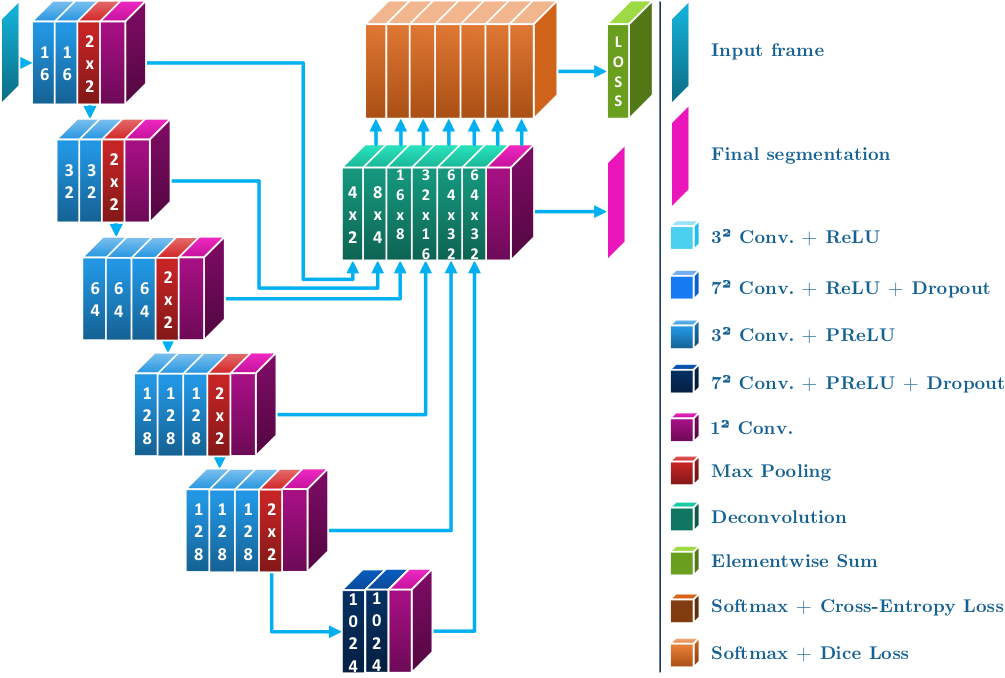

Method 1 was from a team at the National Center for Tumor Diseases (NCT) in Dresden. It consisted of Sebastian Bodenstedt, Isabel Funke and Stefanie Speidel. Their method was based on residual CNNs and the topology of the network can be seen in Fig. 5. Before training, they cropped the black borders off the images, equally removing rows and columns to leave an image of resolution and then downsampled the image to . Random augmentations of increasing the pixel value by , vertical and horizontal flips, zooms of and rotations of degrees. Training was performed for 200 epochs using a categorical cross entropy as a loss function and Adam as the optimizer.